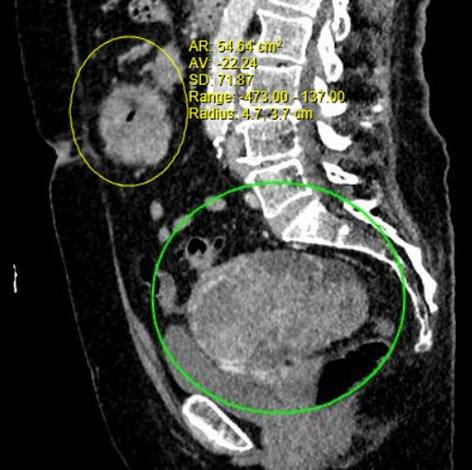

Result: The comparative analysis of the data shows a decrease in the number of presentations in ESU of AC cases during the pandemic, compared to the previous year, most often due to patients' fear of contacting the virus in the hospital environment. The median time between the onset of symptoms and the presentation in the ESU: 2020 – 14 days, 2019 – 5 days. Forms of moderate and severe AC predominated in the pandemic: GradeI—14.28%; GradeII—57.14%; GradeIII—28.57%. In 2019 GradeI—66.39%, GradeII—27.73%, GradeIII—5.88%. Laparoscopic cholecystectomy was attempted for all patients from the beginning, but the complications identified during surgery and severe forms led to a conversion rate in 2020 of 14.28%, compared to 5.88% in 2019. The severity of the cases is also observed in the postoperative complications encountered (perihepatic abscess Fig. 2. Figure 2, wound infection, bile leak; 2019—5.04%, 2020—23.21%), which required surgical reinterventions to solve them (2019: 2.52%, 2020: 10.71%). The number of deaths was significantly higher in 2020 (5.35%), compared to 2019 (0.84%).